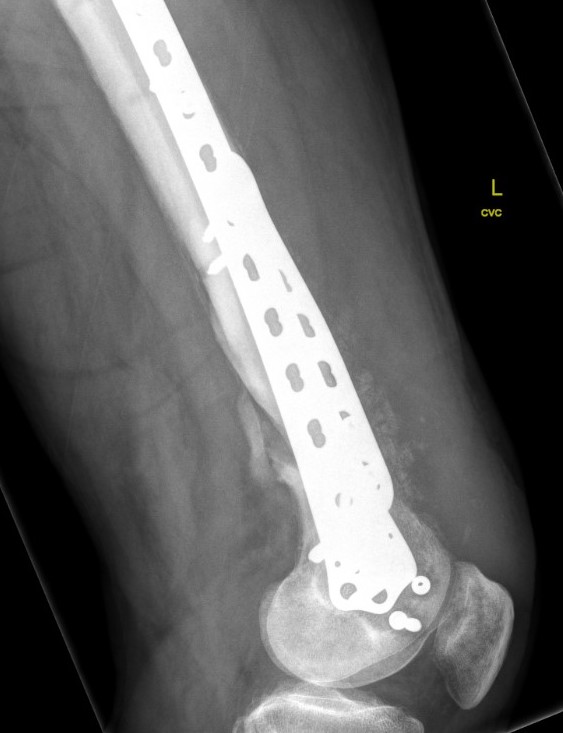

Type C: Complete articular

Xray / CT

Options

Dual Plate

Plate + Retrograde nail

Indications

Significant comminution

Loss of medial cortical buttress